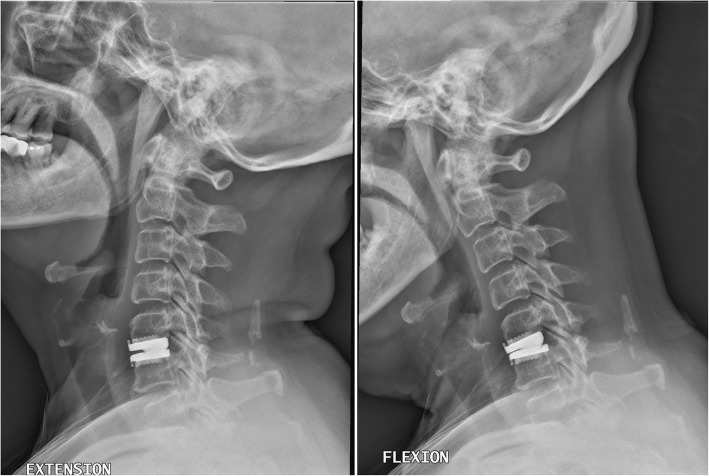

Young patients tended to have increased segmental ROM after CDA, while the elderly patients had a decrease in segmental ROM after the CDA surgery. Overall, the segmental ROM was well-preserved in all the patients after CDA (Table 4, Fig. 2). However, there was a distinct difference in regard to the change of ROM between the two groups. In the elderly group, the segmental ROM at the indexed level tended to decrease within 24 months after surgery, from 6.1 ± 3.67 degrees pre-operatively to 5.6 ± 3.49 degrees post-operatively. In contrast, for the young group, the segmental ROM increased from 7.8 ± 4.16 to 8.3 ± 4.17 degrees after CDA. In other words, the alteration of segmental ROM after CDA was the major distinction between the elderly patients and the relatively younger ones (decrease vs. increase, elderly versus young).

Fig. 2.

A female patient in the elderly group (≥65 years old), who underwent C5–6 cervical disc arthroplasty (CDA) with Prestige LP disc. The range of motion (ROM) at the index level was well-preserved 2 years after CDA